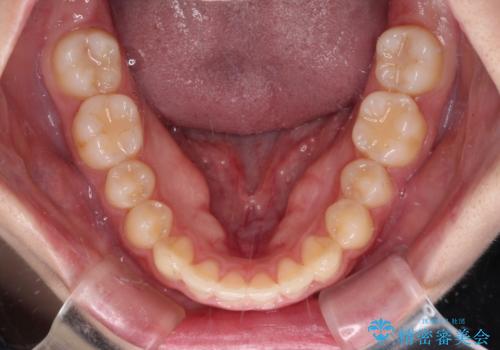

- 八重歯を気にして来院された患者様です。

八重歯のために乳歯が残存していたため、乳歯を抜去して八重歯となっている犬歯を歯列に収めることとしました。

八重歯の移動量が多くなるため、インビザラインと併用してワイヤー矯正を行い、八重歯を改善した後に、上下歯列をインビザラインで整えることとしました。

犬歯は歯根が長くて太いため移動に時間がかかる上に、周囲の歯が八重歯に寄ってきてしまうため、仕上がるまでに期間がかかりました。